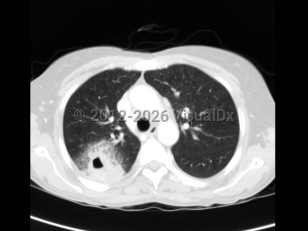

Bacterial infections due to Acinetobacter species are typically encountered in health care settings and can be particularly difficult to treat due to the propensity of the organism to incorporate multiple antibiotic resistance mechanisms. Hospital outbreaks of multidrug-resistant Acinetobacter infections, including carbapenem-resistant Acinetobacter baumannii (CRAB), have been reported. A wide range of infections are possible with this organism, including bloodstream infections, pneumonia (occasionally even community-acquired pneumonia), urinary tract infections, and wound infections (wound infection in soldiers after traumatic injury have been reported).

Patients present with symptoms compatible with the site of infection (for example, patients with pneumonia will have respiratory symptoms compatible with pneumonia). Fever is common. Laboratory studies will frequently reveal leukocytosis. The organism grows readily in standard culture media, and infection can be diagnosed by isolating the organism.